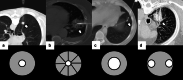

Image-guided percutaneous lung ablation has proven to be a valid treatment alternative in patients with early-stage non-small cell lung carcinoma or oligometastatic lung disease. Available ablative modalities include radiofrequency ablation, microwave ablation, and cryoablation. Currently, there are no sufficiently representative studies to determine significant differences between the results of these techniques. However, a common feature among them is their excellent tolerance with very few complications. For optimal treatment, radiologists must carefully select the patients to be treated, perform a refined ablative technique, and have a detailed knowledge of the radiological features following lung ablation. Although no randomized studies comparing image-guided percutaneous lung ablation with surgery or stereotactic radiation therapy are available, the current literature demonstrates equivalent survival rates. This review will discuss image-guided percutaneous lung ablation features, including available modalities, approved indications, possible complications, published results, and future applications.